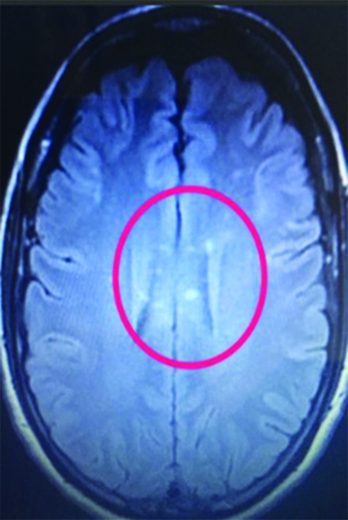

Paciente de 44 años de edad de sexo femenino sin antecedentes clínicos, inicia con deterioro del sensorio de tres semanas de evolución, presentando al examen físico debilidad muscular generalizada, desorientación temporo-espacial, discurso incoherente y conductas bizarras, clasificado como grado III de encefalopatía según la escala de severidad de West Haven. En la resonancia magnética (RM) se observan lesiones múltiples puntiformes como bolas de nieve que confluyen, secuencia de perlas, hiperintensas en secuencia de difusión (DWI) cortico-subcorticales fronto parietal bilateral, cuerpo calloso, unión calloso septal, rodete, hemiprotuberancia y pedúnculo cerebeloso medio derecho en la resonancia magnética (RM Imágenes 1 y 2).

Imagen 1:

RM corte axial de cerebro, (marcado por un anillo rojo) se evidencian lesiones hiperintensas focales y ovoidea, tamaño variable, brillantes, visibles sobre el espesor de cuerpo calloso y en la unión calloso-septal ambos hemisferios cerebrales, aspecto de perlas. Imagen 2: RM corte axial de cerebelo, imagen puntiforme hiperintensa en pedúnculo cerebeloso medio derecho.